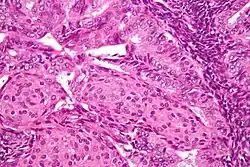

A histopatologia dos cancros do endométrio é altamente diversa. O que é encontrado mais comummente é um adenocarcinoma endometrioide bem diferenciado,[45] que é composto por numerosas glândulas pequenas e aglomeradas com vários graus de atipia nuclear, actividade mitótica e estratificação. Isso geralmente aparece no plano de fundo da hiperplasia endometrial. O adenocarcinoma Frank pode ser distinguido da hiperplasia atípica pela descoberta de invasão estromal clara, ou glândulas "costas com costas" que representam a substituição não destrutiva do estroma endometrial pelo cancro. Com a progressão da doença, o miométrio é infiltrado.[55]